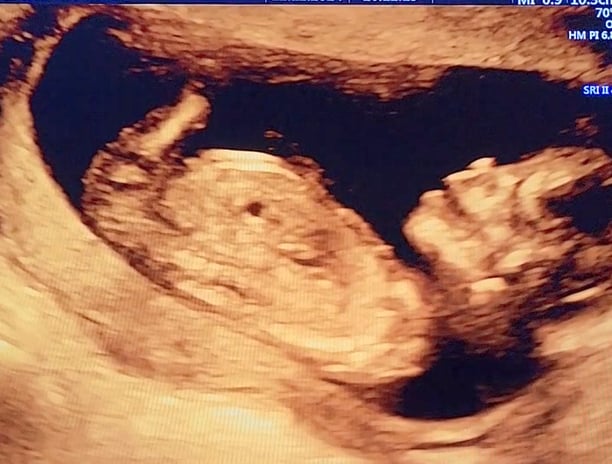

Essa fotinho é do meu primeiro ultrassom! Eu não tinha nem o tamanho de uma azeitona, e já me mexia todo, abria a boca e meu coração já batia bem forte!